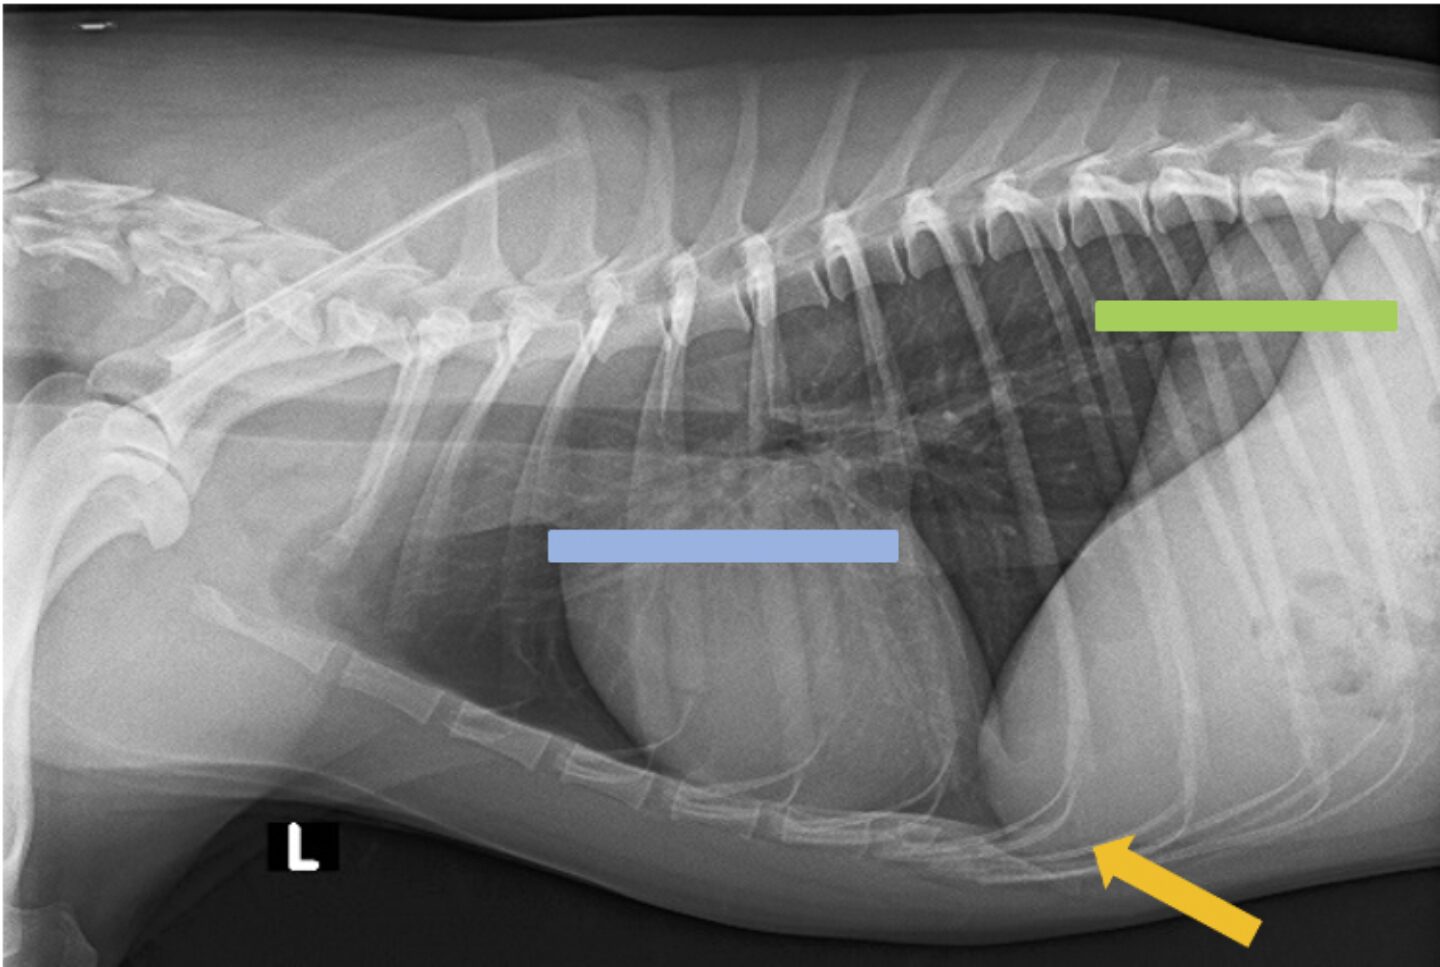

Der Thoraxerguss bei der Katze

Der Thoraxerguss ist eine häufige Ursache für Atemnot bei Katzen. In zwei Studien mit jeweils 90 bzw. 106 Katzen mit Atemnot konnte bei etwa 30 % ein Thoraxerguss als Auslöser nachgewiesen werden (1, 2). Es handelt sich hierbei um eine vermehrte Ansammlung von Flüssigkeit im Pleuraspalt, also zwischen dem viszeralen und dem parietalen Pleurablatt, die die Ventilation und die Oxygenierung stark beeinträchtigt. Unter normalen Umständen befinden sich nur wenige Milliliter Flüssigkeit in diesem Spalt, die als eine Art Gleitfilm fungieren und eine reibungslose Bewegung der Pleurablätter während der